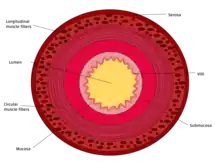

This cross section diagram shows the 4 layers of the small intestine wall.

LayerDuodenumJejunumIleum

Serosa1st part serosa, 2nd–4th adventitiaNormalNormal

Muscularis externaLongitudinal and circular layers, with Auerbach's (myenteric) plexus in betweenSame as duodenumSame as duodenum

SubmucosaBrunner's glands and Meissner's (submucosal) plexusNo BGNo BG

Mucosa: muscularis mucosaeNormalNormalNormal

Mucosa: lamina propriaNo PPNo PPPeyer's patches

Mucosa: intestinal epitheliumSimple columnar. Contains goblet cells, Paneth cellsSimilar to duodenum, but the intestinal villus is longSimilar to duodenum, but the intestinal villus is short